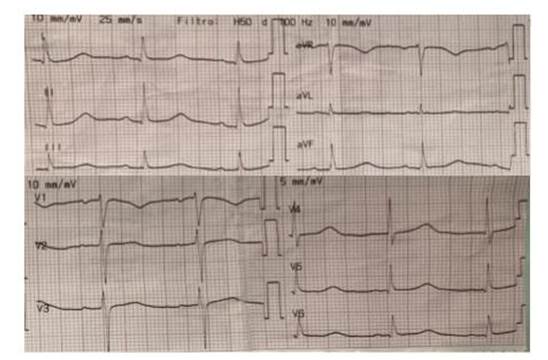

Ingresa en octubre de 2023 por historia de cuatro días de evolución dada por disnea de esfuerzo clase funcional II acompañada de disnea de decúbito, en apirexia. En el examen físico se encontraba lúcido, sin elementos de focalidad neurológica, normocoloreado, sin lesiones de piel. En lo cardiovascular, no se veía ni palpaba choque de punta, se encontraba normotenso, con un ritmo cardíaco regular de 60 cpm y un soplo sistodiastólico de intensidad 5/6 con máxima auscultación en el foco aórtico, irradiado a todo el precordio, con R2 abolido y frémito. No presentaba signos clínicos de insuficiencia cardíaca. El electrocardiograma evidenciaba alteraciones de la repolarización en cara lateral y la radiografía de tórax presentaba elementos de hipertensión venocapilar (Figura 1y2).

Figura 1 Electrocardiograma al ingreso. Ritmo sinusal 60 cpm, sobrecarga auricular izquierda, bloqueo AV de primer grado con intervalo PR 210 ms, eje eléctrico medio + 60°, QRS 80 ms. A nivel del segmento ST-T se observa rectificación de V4-V6. QTc normal.